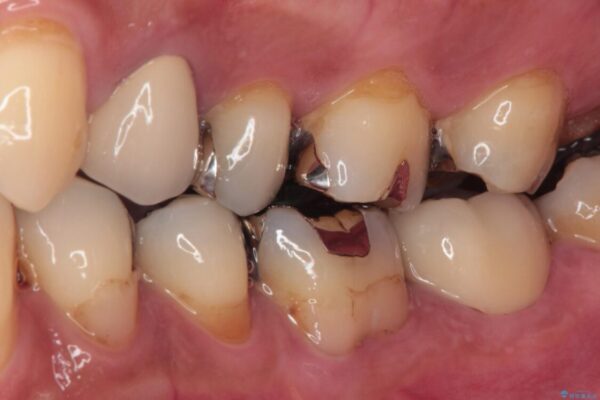

痛みを感じ近医を受診したものの、違和感が改善しないとのことで来院された患者様です。

診査をしたところ、神経組織に影響を及ぼすような大きな虫歯があることが分かりました。

治療前

• 治療をしても違和感の続く奥歯 神経を極力残した虫歯治療 治療前画像